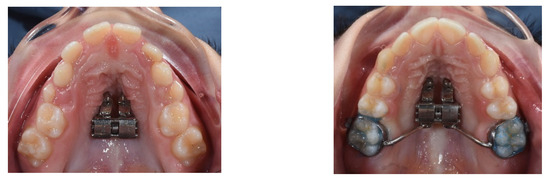

4.3. Treatment Strategy

4.4. Treatment Progress